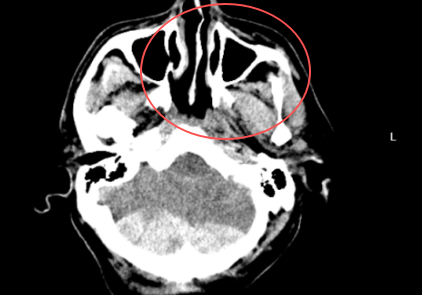

近日,紹興袍江醫(yī)院急診科緊急接收了一名由120轉(zhuǎn)運(yùn)來(lái)的意識(shí)不清危重患者。經(jīng)快速檢查,患者被確診為創(chuàng)傷性枕部跨竇硬膜外血腫、創(chuàng)傷性蛛網(wǎng)膜下腔出血、左側(cè)額顳部硬膜下血腫,同時(shí)合并全身多處損傷,病情危急。罕見(jiàn)“對(duì)沖傷”疊加小腦創(chuàng)傷,病情半小時(shí)內(nèi)急轉(zhuǎn)直下該患者所受損傷為顱腦“對(duì)沖傷”,即頭部前后方同時(shí)受力受損,是多發(fā)傷中的常見(jiàn)類(lèi)型。更棘手的是,患者合并小腦創(chuàng)傷——這一創(chuàng)傷類(lèi)型在所有顱腦創(chuàng)傷中占比僅2%-5%,臨床處理難度極大。圖片有可能引起不適,慎點(diǎn)患者入院后病情迅速惡化,半小時(shí)內(nèi)即2025-10-07